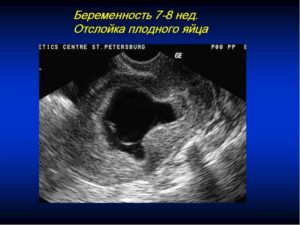

Также плодное яйцо выступает 1-й структурой, различаемой на ультразвуковом исследовании и помогающей подтвердить наличие беременности. Обладает формой овала или круга, увеличивается в размерах с течением времени.

Исходя из диаметра плодного яйца, представляется возможной установка точного термина беременности, а также ее возможных нарушений (доктор оценивает форму и благодаря полученным сведениям выявляет состояние маточного тонуса).

Вместе с отслоением хориона начинают разрываться сосуды, за счет которых он внедрился в матку, в этой области образуется гематома. Именно это и будет самым первым симптомом отслоения, которое обнаруживается на ультразвуковой диагностике. В случае частичной или не сильно выраженной отслойки, гематома может быть единственным проявлением данного патологического состояния.

УЗИ-исследование – это основной способ диагностики этой патологии наряду с общим осмотром врача гинеколога. С помощью ультразвука доктор сможет увидеть наружную оболочку плодного яйца и оценить, в каком она состоянии. Также для него будет важным наличие гематомы между плодным яйцом и хорионом, то есть его оболочкой.

Состояние плода также необходимо оценить. С шестой недели возможно прослушать его сердцебиение. А само плодное яйцо на УЗИ можно обнаружить уже к концу первого месяца беременности.